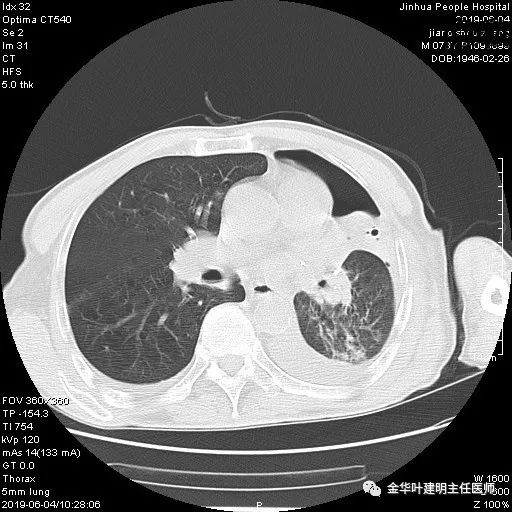

考虑左侧大量胸腔积液,遂进一步胸部CT检查:

以上是肺窗表现,下面为纵隔窗影像: